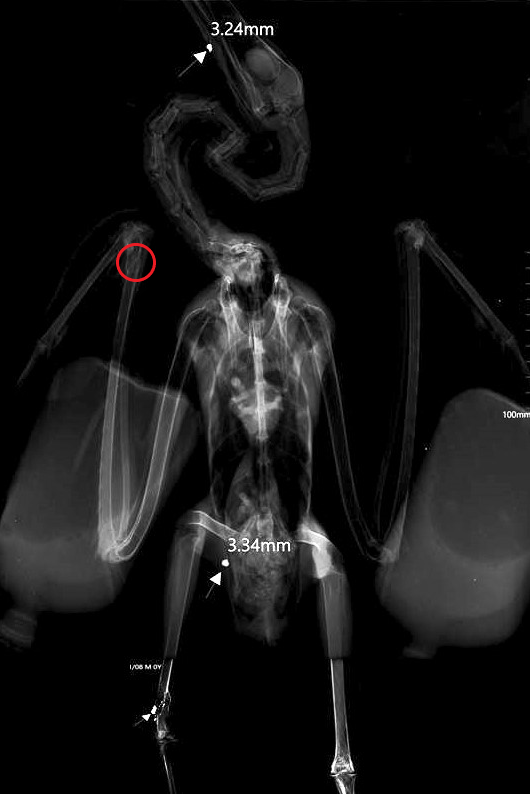

| Raio-X da águia-calçada. |